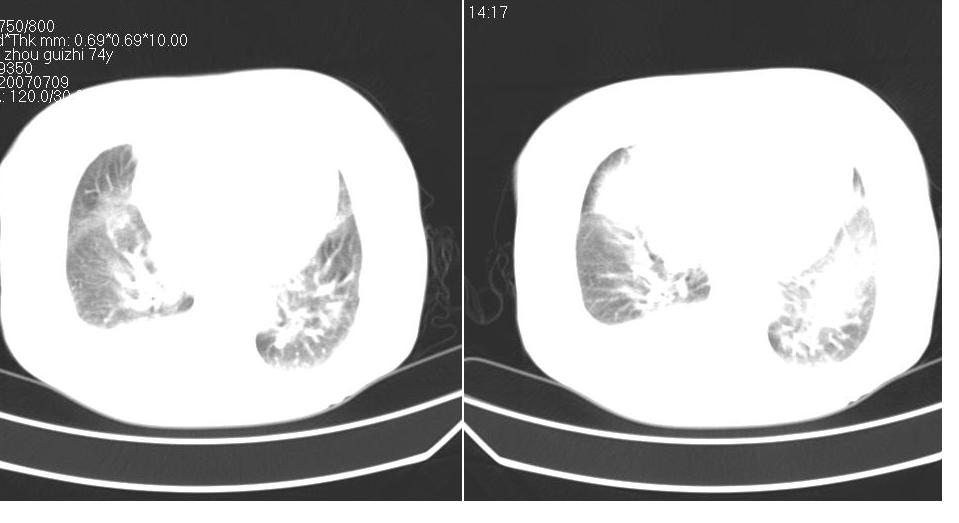

以下是引用liaizhi在2007-7-11 15:41:00的发言:[br]两肺纹理增粗,肺门影增大,气管支气管通畅。升主动脉壁及冠状动脉壁钙化。左房左室稍扩大。心包积液,胸腔积液。考虑冠心病并心功能不全,肺水肿,胸腔积液。

以下是引用zhangzhongshou在2007-7-11 13:16:00的发言:[br]1、冠状动脉钙化[br]2、心包积液[br]3、右侧胸腔积液[br]大家都考虑心衰,冠状动脉钙化、肺纹理增强,胸腔积液、心包积液,表面上是支持,但是为什么右侧有较多积液,左侧没有呢? 如果用结核性胸膜炎,并结核性心包炎也可解释,请楼主进一步提供临床资料。

以下是引用yanghaochen88在2007-7-11 9:00:00的发言:[br]冠心病、心包积液、胸水,心衰结合临床。